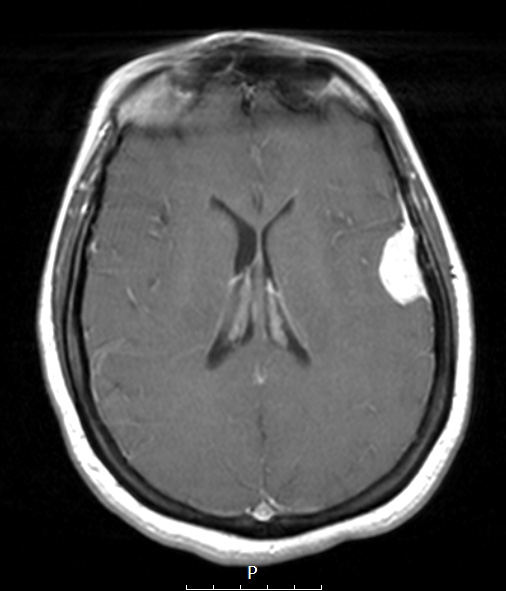

Washington University Experience | NEOPLASMS (MENINGIOMA) | Secretory | 17A3 Meningioma, lipidized (Case 17) T1W - Copy

17A3 Meningioma, lipidized (Case 17) T1W - Copy

This T1-weighted image shows contrast enhancement.